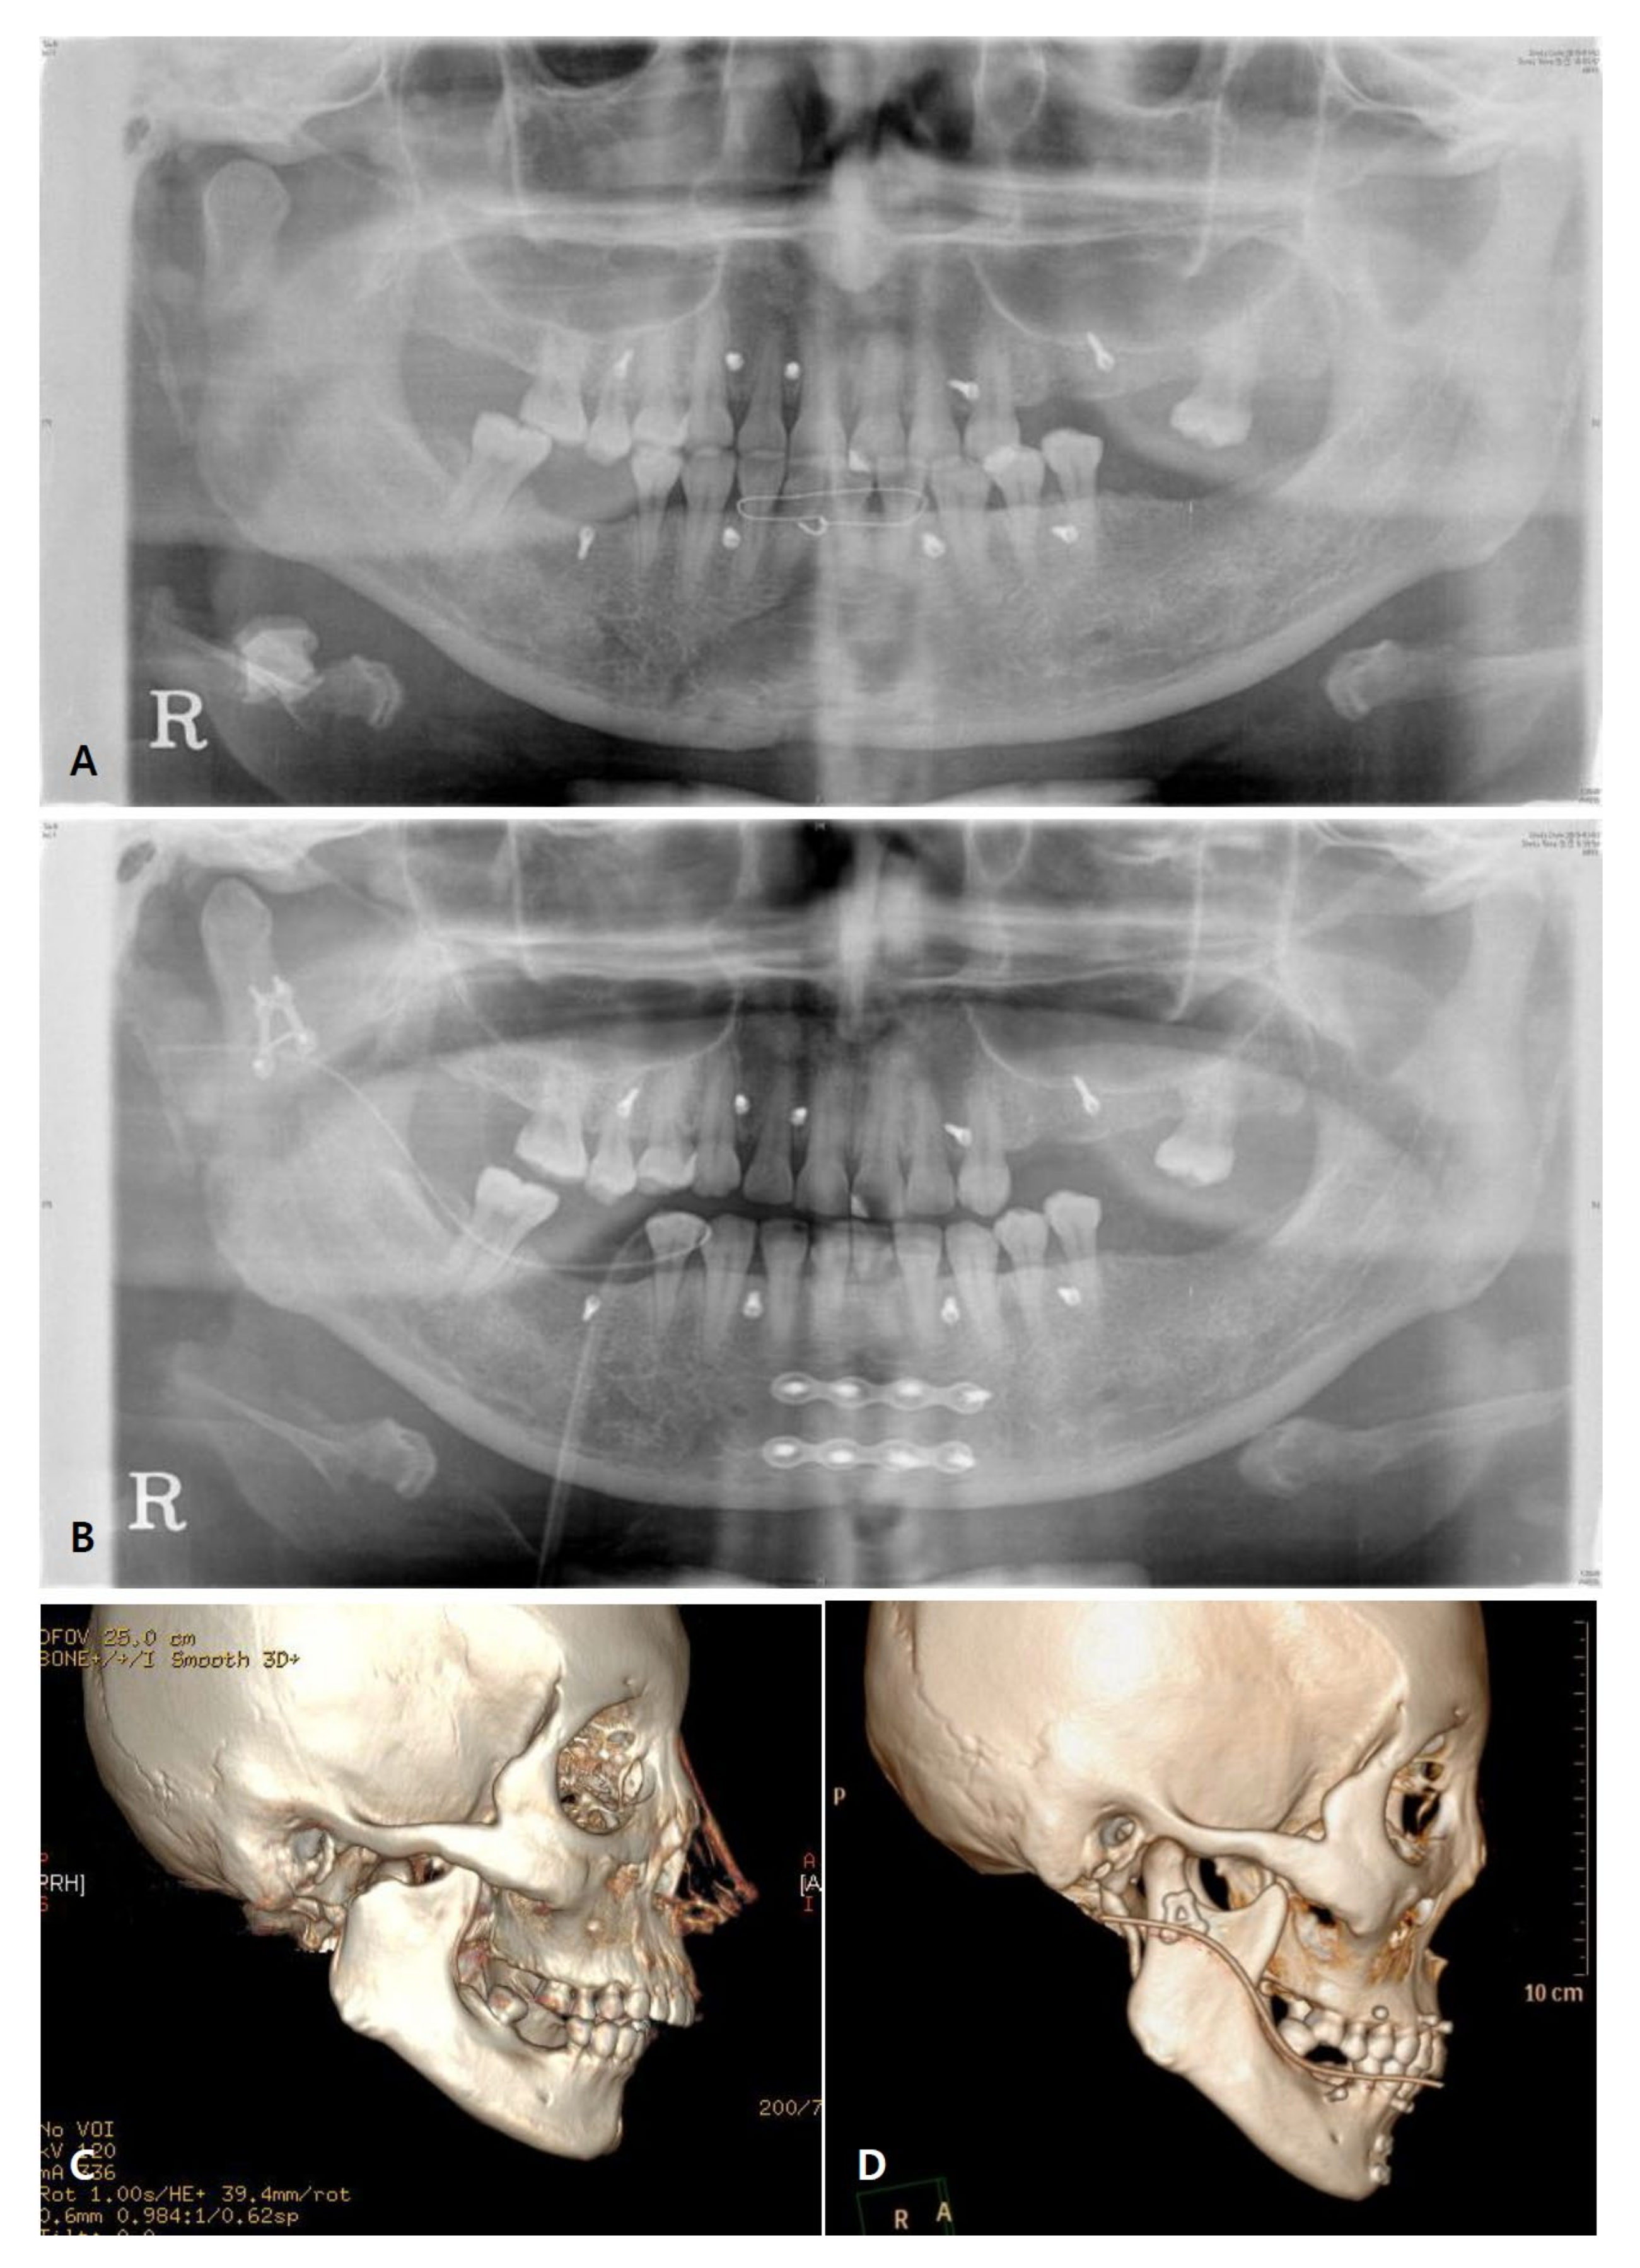

3.3. Radiographic Evaluation

| Variables | Non-Operated Side (n = 18) | Operated Side (n = 18) | p-Value * | |

| Length (mm) | Mean ± SD | 65.68 ± 6.77 | 65.02 ± 6.48 | 0.205 |

| Median (min–max) | 65.33 (52.10–79.40) | 66.77 (48.16–74.13) | ||

| Angle (n°) | Mean ± SD | 166.31 ± 7.10 | 164.95 ± 8.26 | 0.099 |

| Median (min–max) | 168.10 (143.00–175.20) | 165.30 (142.50–179.50) | ||